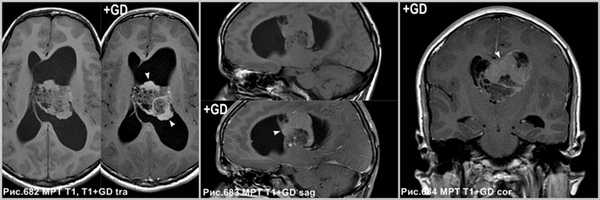

Дифференциальная диагностика

Эпендимома чаще встречается в детском возрасте, в основном, поражает IV желудочек и распространяется через желудочковые отверстия (рис.685).

Хориоидпапиллома (рис.686) встречается, главным образом, у детей; типично интенсивное контрастирование опухоли и внутриопухолевого питающего сосуда.

Субэпендимома обычно встречаются в IV желудочке, поражает людей старшего возраста (рис.687).

Эпендимома в виде солидного образования в правом боковом желудочке (головка стрелки на рис.685). Папиллома сосудистого сплетения в центральном отделе левого бокового желудочка (звёздочка на рис.686), окруженная перифокальным отёком (головки стрелок на рис.686). Субэпендимома левого бокового желудочка (стрелки на рис.687).